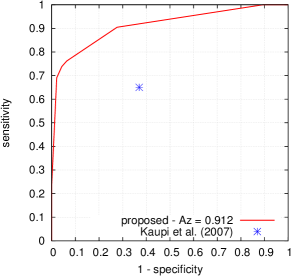

Given a target lesion type, Kauppi et al. (2007) proposed a standardized procedure to evaluate the performance of a lesion detector, at the image level, in the DiaretDB1 dataset. In this purpose, one probability map was constructed per image: this map was obtained by averaging, at the pixel level, confidences from all four experts for the target lesion type. If and only if this map contains at least one pixel with an average confidence level above 75 , then the image is considered to contain the target lesion. Based on this criterion, a receiver-operating characteristic (ROC) curve can be constructed for the lesion detector.

FROC curves are reported in Fig. 6 for ‘net B’; areas under the limited FROC curve for all three ConvNets are summarized in Table 3. It appears that the number of false alarms is rather large, particularly in the case of microaneurysm detection. The reason is that human experts primarily segmented the most obvious lesions, while screening algorithms need to focus on the most subtle lesions as well. In other words, many true lesions are counted as false alarms. Of course, this comment also applies to competing automatic solutions. To show the value of our detections, the proposed solution was compared in Fig. 7 to results reported in the literature, following the DiaretDB1 standardized procedure (see section 5.3.2). Most authors reported a single (sensitivity, specificity) pair: this is what we reported in Fig. 7. Some authors reported ROC curves; in that case, we also reported a single (sensitivity, specificity) pair: the one closest to the (sensitivity = 1, specificity = 1) coordinate. Note that all competing solutions (Kauppi et al., 2007; Yang et al., 2013; Franklin and Rajan, 2014; Kumar et al., 2014; Bharali et al., 2015; Mane et al., 2015; Dai et al., 2016) are trained at the lesion level, while ours is trained (in Kaggle-train) at the image level.

Three ConvNets were trained to detect referable DR in the Kaggle-train dataset, using the proposed heatmap optimization procedure. Then, we evaluated how well those ConvNets could detect lesions in the DiaretDB1 dataset, without retraining them. For lesion detection at the image level, they outperformed previous algorithms, which were explicitly trained to detect the target lesions, with pixel-level supervision (see Fig. 7). This superiority was observed for all lesions or groups of lesions, with the exception of ‘red lesions’. Experiments were also performed at the lesion level: for all lesion types, the proposed algorithm was found to outperform recent heatmap generation algorithms (see Table 3). As illustrated in two examples (see Fig. 9 and 10), the produced heatmaps are of very good quality. In particular, the false alarms detected on the vessels, in the vicinity of true lesions in the unoptimized heatmaps ( maps), are strongly reduced with sparsity maximization (, , ). These experiments validate the relevance of image-level supervision for lesion detectors, but stress the need to optimize the heatmaps, as proposed in this paper. Note that detection performance is not affected much by image quality: very good detections are produced in the blurry image obtained with a low-cost, handheld retinograph (see Fig. 10). This is a very important feature, which opens the way to automated mobile screening. However, it can be observed that the ‘AlexNet’ architecture, which achieves moderate DR detection results, also achieves poor detection results at the lesion level, even after heatmap optimization (see Table 3): to ensure good detection performance at the lesion level, the proposed optimization framework should be applied to ConvNet architectures that achieve good image-level performance.